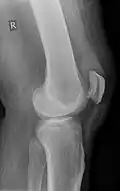

Weitere Bildbeispiele

Teilriss der Sehne, die auch im Röntgenbild aufgetrieben (eingeblutet) sichtbar ist -